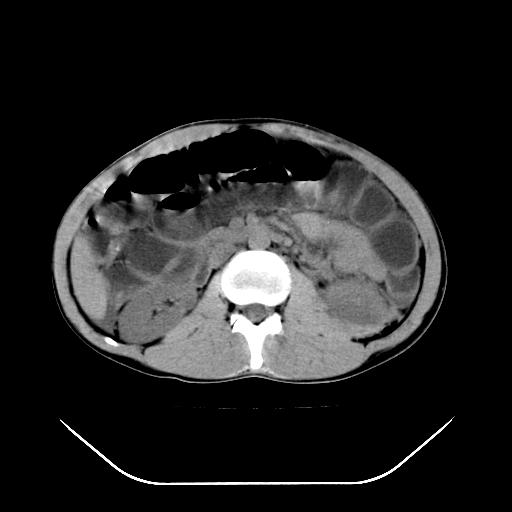

m-25y 高空堕落 12 月5号

12月7号病人尿量200ml/24h 急查双肾ct

左肾挫裂伤并肾周血肿;

左肾挫裂伤并肾周血肿

支持 : 左肾挫裂伤并肾周血肿

支持:1、左肾挫裂伤并肾周血肿;

2、少量腹水;

3、左肾旋转不良;

4、反射性肠淤张。

3、反射性肠淤张。

综上所述,考虑1:左肾挫伤并包膜下血肿2:少量腹腔积液3:肠梗阻的可能

除了1:左肾挫裂伤并肾周血肿;

2:少量腹水

第二次ct检查后:临床医生腹水穿刺后考虑肠系膜动脉破裂,后实行剖腹探查:于空肠距离十二指肠90cm处发现肠管破裂,破裂口较小;修补后关腹。